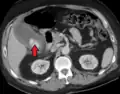

Acute cholecystitis with gallbladder wall thickening, a large gallstone, and a large gallbladder- Significant gallbladder wall thickening[29]

- Significant gallbladder wall thickening[29]

Right upper quadrant abdominal ultrasound is most commonly used to diagnose cholecystitis.[1][26][27] Ultrasound findings suggestive of acute cholecystitis include gallstones, pericholecystic fluid (fluid surrounding the gallbladder), gallbladder wall thickening (wall thickness over 3 mm),[28] dilation of the bile duct, and sonographic Murphy's sign.[13] Given its higher sensitivity, hepatic iminodiacetic acid (HIDA) scan can be used if ultrasound is not diagnostic.[13][14] CT scan may also be used if complications such as perforation or gangrene are suspected.[14]